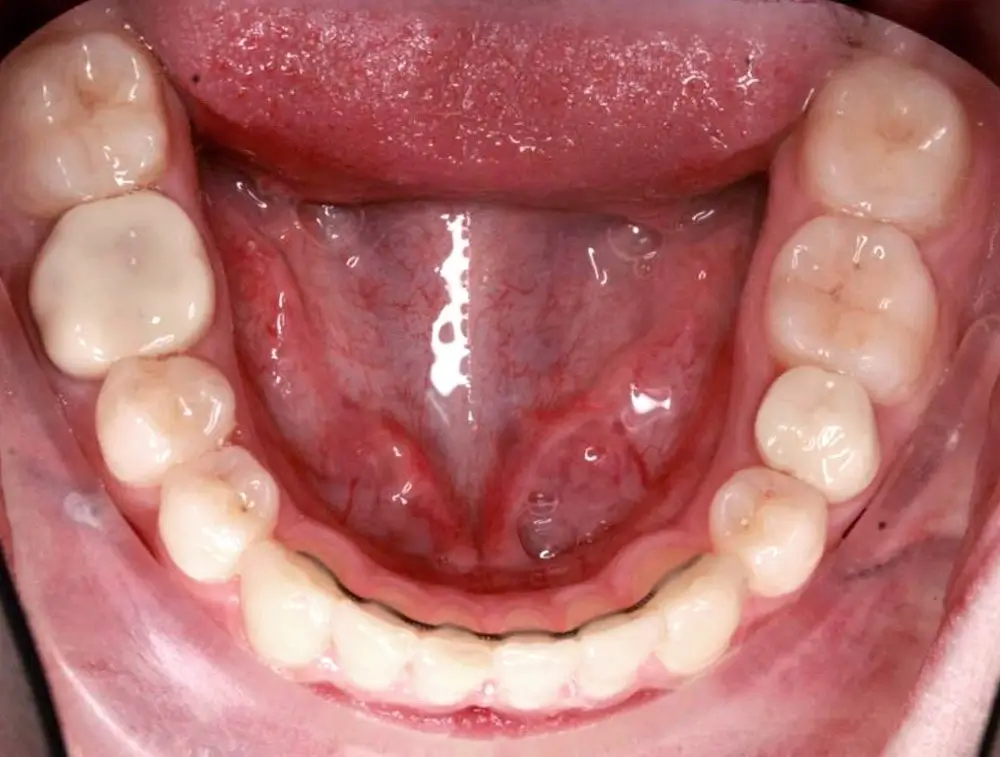

Кейс 9

Бирковская Екатерина Александровна

Количество кап ВЧ 23

Количество кап НЧ 23

ДО

ПОСЛЕ